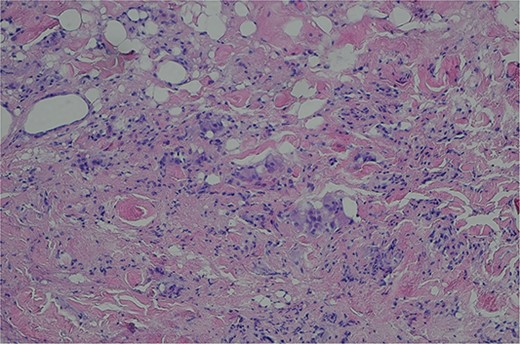

A 19-year-old male presented with a small mass on his left scalp since infancy and denied any trauma history. The tumor had gradually increased in the recent two years, accompanied by pain after strenuous exercise. It had grown to a diameter of 20 × 10 mm on admission and was soft and painful to the touch. The scalp above the tumor was covered with hair of average density, without sinus orifice and pus discharge. Surgical excision was successfully performed on the patient under local anesthesia and primary suture. Gross specimen showed the mass as cystic, containing a large amount of cloudy fluid and hair (Fig. 1). Histopathologic examination of the specimen showed inflamed granulation tissue with scattered foreign body giant cells (Fig. 2).

Histopathologic examination of the specimen showed inflamed granulation tissue with scattered foreign body giant cells (H&E; ×200).